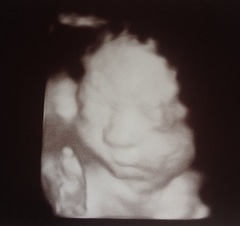

First consultant appt today, she was def having a good look at babes heart, you could see her getting her learning on, she was quite fascinated. Anyway I got a cheeky free 4d scan so, as we've not had many scan pics in a while, here's mine from today @ 28+5

August 2016 number 5 - waddling towards the third trimester!